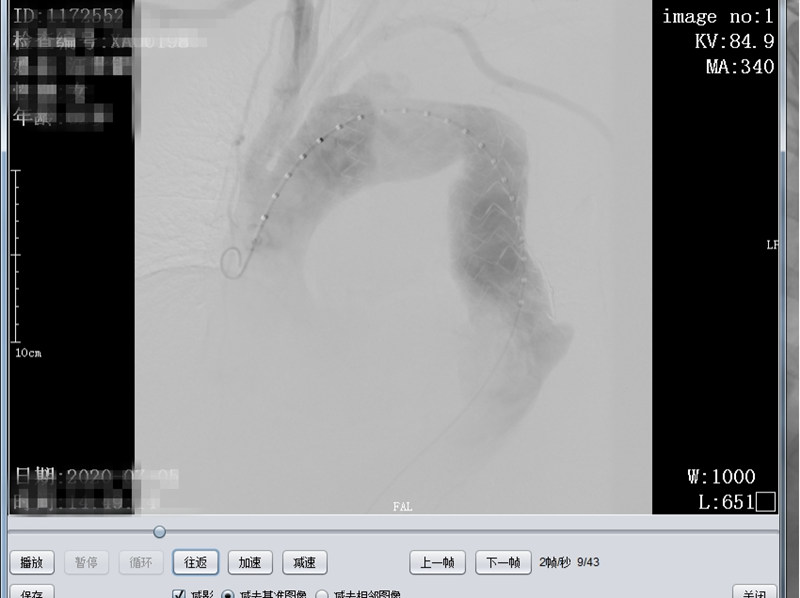

患者朱某,女,72岁,家住我县全军乡,6月22日下午突发胸背部剧痛至我院急诊科就诊,行胸部CTA检查考虑主动脉夹层(Debakey  III型),急请我科会诊。会诊后以主动脉夹层收住介入科,积极给予稳定血压、镇痛治疗。因该患者为先天性失聪失语,沟通十分困难、不畅,祝国臣副主任通过患者女儿耐心与患者沟通,详细询问病情,仔细检查患者体征,并与患者家属说明患者的病情与风险,患者家属了解病情后,十分感激祝国臣医生,决定手术治疗。我科积极完善相关术前准备及手术所需材料,于 7月5日在DSA下行“主动脉、左锁骨下动脉造影+分支型覆膜支架腔内隔绝术”,术中患者破口及真假腔显示明确,破口位置与左锁骨下动脉距离较近,给手术带来一定的困难,根据患者术中造影情况,制定详细手术方案,既保证覆膜支架安全成功释放,又保证不影响左锁骨下动脉血供。术后患者病情平稳,现患者血压、心率稳定,患者胸背部疼痛症状消失。

术前CT显示主动脉夹层真假腔及破口位置

术中造影明确真假腔位置及与周围大血管关系

术后造影假腔消失,左锁骨下动脉显示良好,支架周围未见造影剂外溢(内瘘)征象